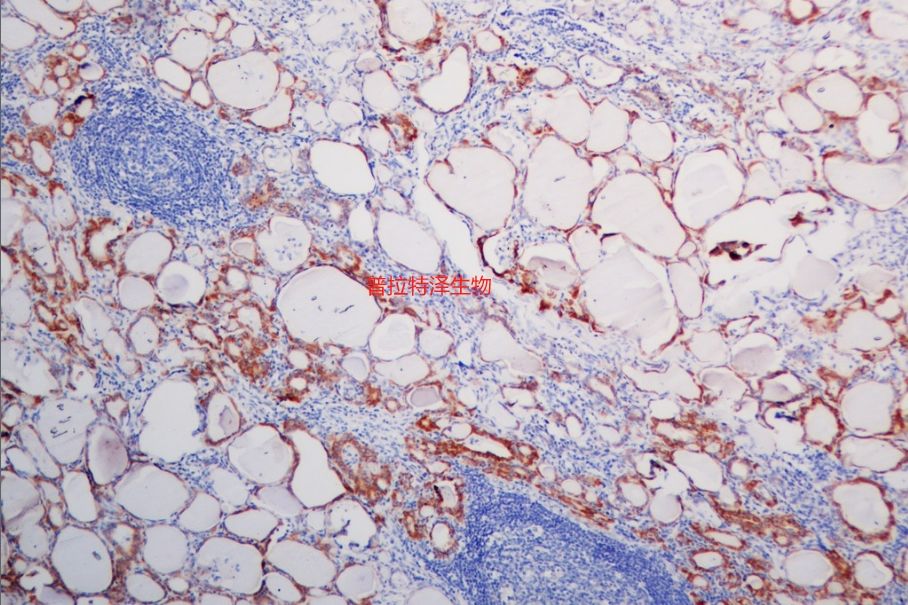

原位雜交是一種在細胞或組織水平上檢測特定核酸序列的技術。然而,在實際應用中,原位雜交實驗常常會遇到一些問題,如非特異性染色、背景信號過高、假陽性或假陰性結果等。普拉特澤生物承接原位雜交等病理染色相關服務上萬例,積累了操作大量經驗,為大家詳細分享原位雜交常見問題的分析與對策,同時為廣大科研工作者開展線上的理論培訓與線下實操,可承接染色實驗外包服務。